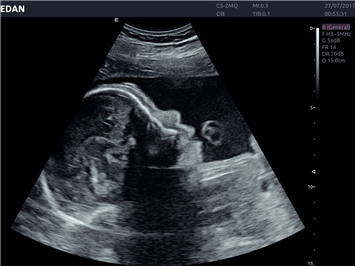

• Автоматизированные измерения в акушерстве

• Акушерства и гинекологии

Гинекология:

Да

3D/4D: